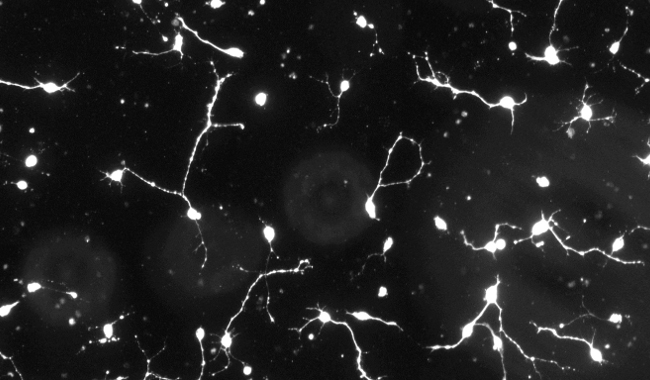

神經(jīng)突增生圖像分析

神經(jīng)系統(tǒng)是一個(gè)復(fù)雜的神經(jīng)元網(wǎng)絡(luò),它的正確運(yùn)作高度依賴于神經(jīng)元向神經(jīng)元連接的適當(dāng)發(fā)育;因此,神經(jīng)回路的形成非常依賴于突起生長(zhǎng)過(guò)程的正確進(jìn)化。突起生長(zhǎng)是神經(jīng)突起形成和發(fā)展的復(fù)雜而關(guān)鍵的過(guò)程,其故障涉及一系列的神經(jīng)元疾病和疾病,如阿爾茨海默病和帕金森,因此它構(gòu)成了神經(jīng)病學(xué)和精神病學(xué)研究的主要焦點(diǎn)之一。